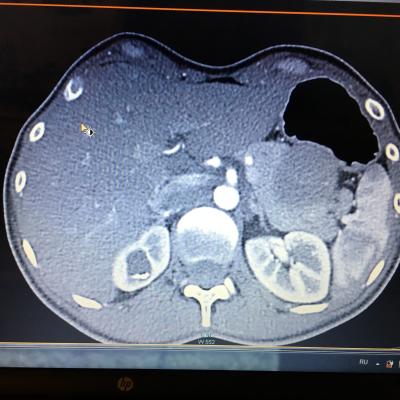

Здравствуйте,помогите, пожалуйста, с расшифровкой кт почек с контрастом. Насколько я поняла, в левой почке маленький камешек. А что за образование в правой почке? Киста с кальцинированной стенкой или камень? Спасибо за ответ!

Здравствуйте! На последнем снимке - больше данных за конкремент. Но при описании снимков должны определяться плотность образования, и нет изображения ни одного фрагмента ни одного из мочеточников. И самих снимков обычно бывает больше. Недостаточно данных для заключения.